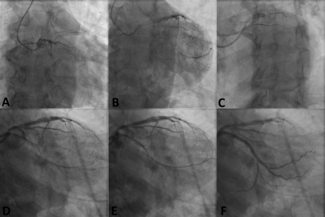

A 60-year-old man was referred for percutaneous coronary intervention of a proximal left circumflex chronic total occlusion with distal filling via epicardial collaterals from the left anterior descending artery. The 30-mm lesion had a...